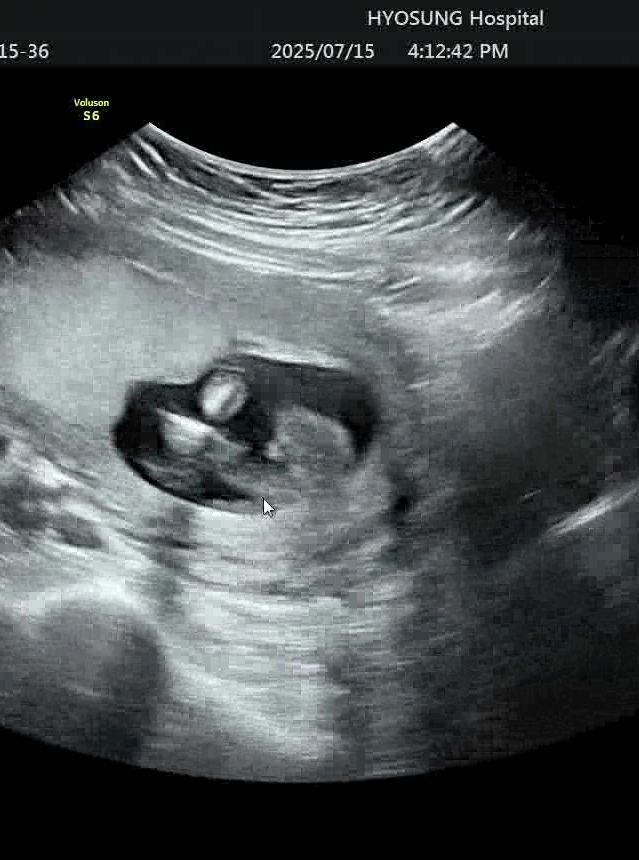

사진이 2장 안올라가서 헷갈리는 사진 1장 올려봅니다. 딸같다 해주셨는데 동영상보다보니 뭔가 튀어난게 보여서요ㅠㅠ 16주 4일 동영상입니다.

엇.....전 아들확정인데 저희애꺼랑 비슷한거같아용...그래도 촘파샘이 더 정확하실테니 딸일 수도 있겠죠??

애매하죠?ㅋㅋㅋㅋ 99% 딸이라더라구요.

그럼 저건 탯줄이던지 한가봐요!!! 축하드려요ㅎㅎㅎ전문가가 정확하죠!!!

그렇겠죠? ㅋㅋㅋ 감사해요! 그래도 반전은 있을 수 있다고 하니 20주나 되야지 정확할 것 같아요 ㅋㅋ